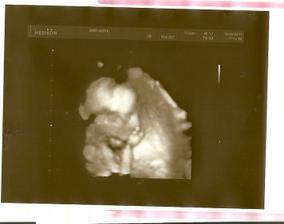

Pořídíme Míše Ríšu 🙂

tak se nám zadařilo počít sourozence, opět to byl fofr, první měsíc, takže opět trochu šok i když příjemný

zatím všechno vypadá krásně, mamince je dobře, doktoři jí hlídají na všech frontách, tak snad se nám tentokrát podaří dočkat se termínu 22.2.2011 🙂